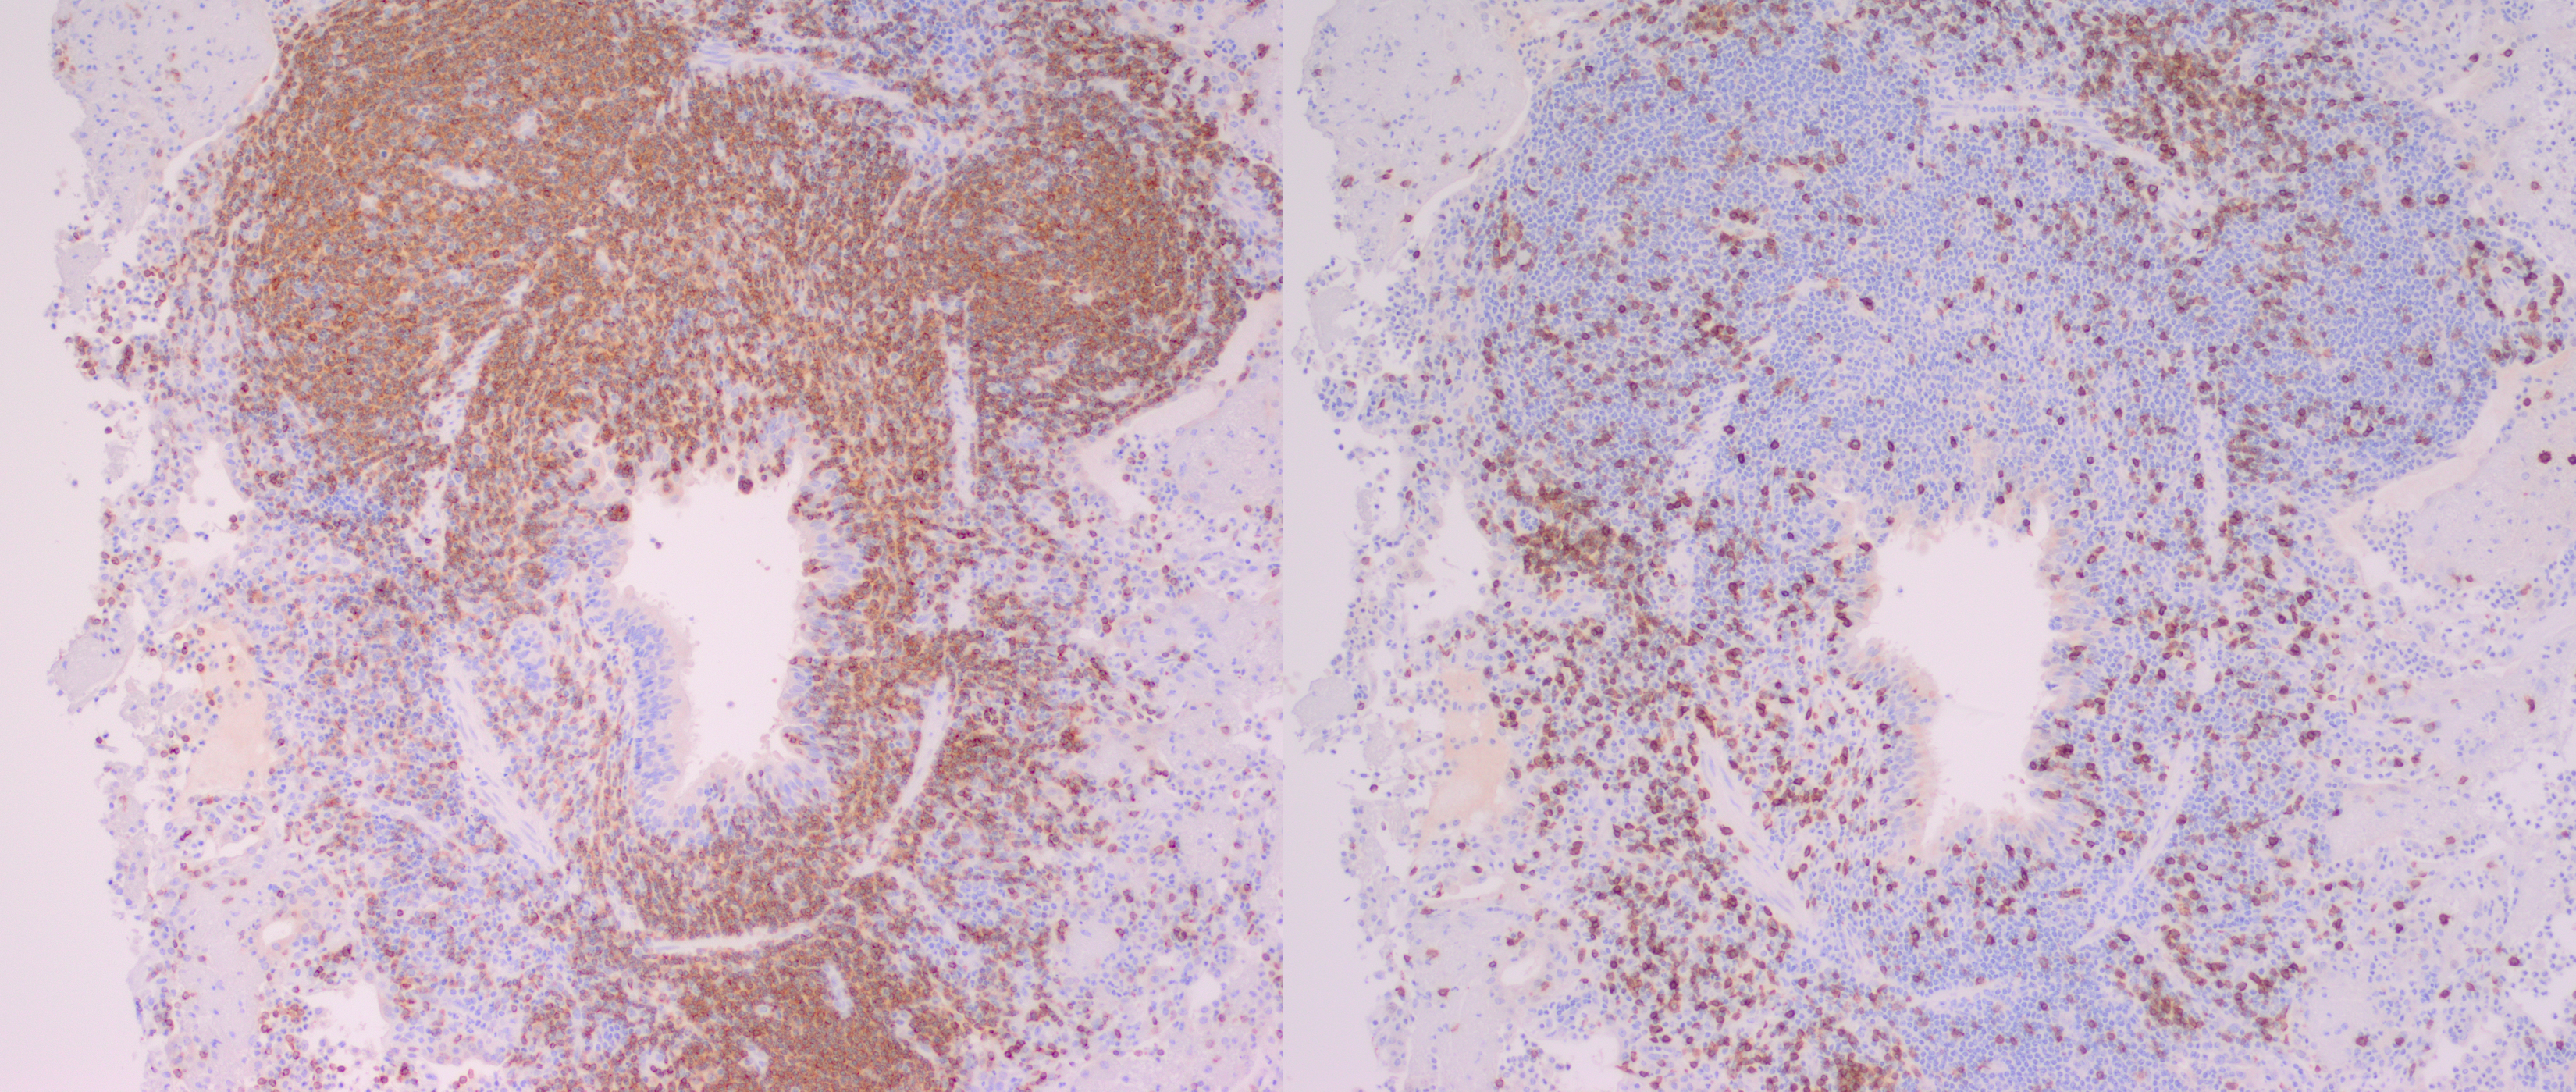

Immunohistochemical markers

|

Marker |

Cell type |

Tissue |

Number of positive cells |

Positive cell distribution |

CD79b |

B Cell |

Lung |

+++ |

Majority of cells within neoplastic infiltrate, scattered cells within peribronchial and peribronchiolar spaces, interlobular and alveolar septae and alveolar lumen |

Lymph node |

The majority of cells within the cortex and moderate numbers (30-50% of cells) within the medulla |

||

Spleen |

Majority of cells within red and white pulp |

CD3 |

T Cell |

+ |

Scattered throughout parenchyma, and small numbers accompanying neoplastic infiltrate |

++ |

Moderate numbers multifocally throughout the medulla |

Predominantly around blood vessels |

In this case, neoplastic cells were also found in the liver, spleen and heart of the camel. No neoplastic cells were found in the kidneys or in two sections of bone marrow (rib and sternum). The presence of atypical lymphocytes within the peripheral blood collected at the initial clinical examination greatly aided the diagnosis of lymphoma or leukemia in this case (Figure 1) and allowed the clinician to understand why this animal did not improve like the others in the herd once nutrition was improved. The neoplastic cells observed in the peripheral blood was suspected to be secondary to the lymphoma, given that no neoplastic cells were found within the bone marrow of the bones examined histopathologically. Leukemia is a feature of less than 20% of lymphomas in animals and is more commonly a feature of T-cell lymphomas.9 Leukemia is most likely observed when the lymphoma invades the bone marrow or spleen, the latter of which contained neoplastic cells in this case.9 In this case a B-cell phenotype was confirmed via immunohistochemistry (Figures 7-11).There are only a few reports in the literature describing lymphoma in dromedary camels. Similar to this case, the disease is typically reported in adult animals (>7 years) and has been reported in both male and female camels. Common clinical presentations include weight loss, anorexia, polyuria and polydipsia, with one report also describing peripheral lymphadenopathy and bilateral masses in the conjunctiva of one animal.3,4,6 Peripheral lymphocytosis, sometimes with significant atypia in circulating lymphocytes and lymphoblasts, has been reported occasionally but is not always a feature of the disease in dromedary camls.3,7

In contrast to this case, all cases in the literature from dromedary camels were identified as T-cell lymphomas. In those cases, lymphocyte lineage identification was performed using immunohistochemistry and identified the neoplastic cells as CD3 (pan T-cell) positive and either CD20 or CD79a (pan B-cell markers) negative.3,4 More recently, flow cytometry has been used to further classify a multicentric T-cell lymphoma as a gd T-cell lymphoma and a combination of CD4 and WC-1 markers.4 Other markers which have been used in the literature to differentiate round cell neoplasms in camelids include PAX-5, CD79b (B-cell markers), CD5 (T-cell marker), MUM1 (plasma cell marker), CD18 and CD68 (histiocyte markers).1,4,6,8